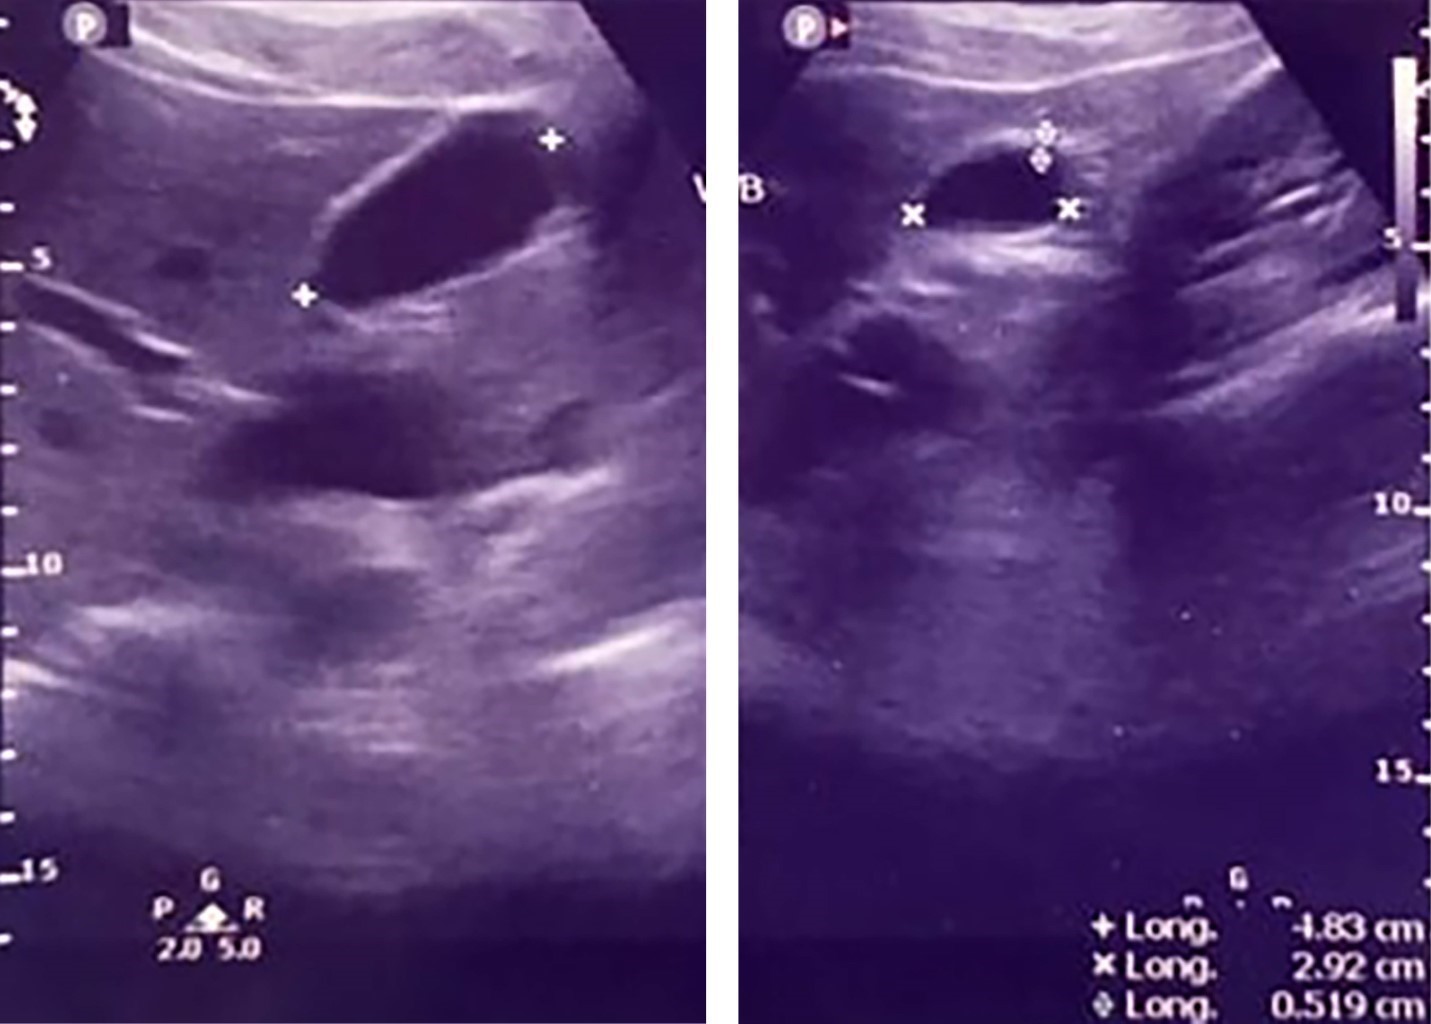

Figure 1